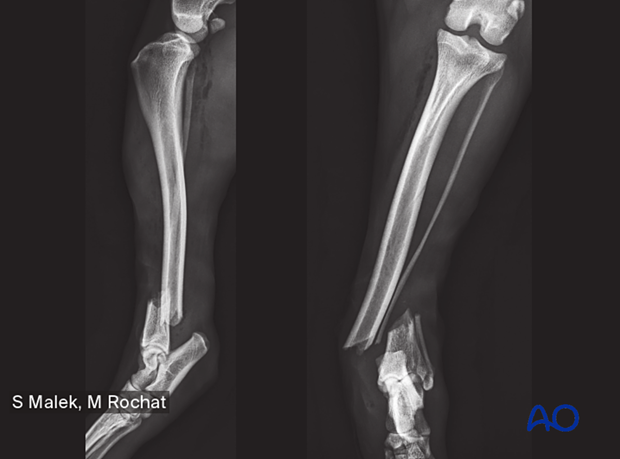

To help identify the fractures, x-rays of most fracture types have been included in the diagnosis section, and the fixation techniques have been enriched with case examples with pre- and postoperative, and follow-up x-rays.

43-A1 Simple extraarticular fracture of the distal tibia: